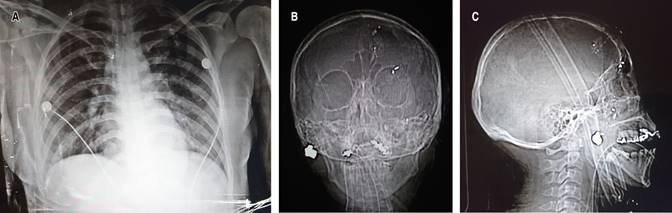

La radiografía de tórax no muestra alteraciones, en las radiografías de cráneo se evidencia proyectil de arma de fuego (PAF) a nivel de pómulo izquierdo en la radiografía anteroposterior y lateral de cráneo (Figura 1).

Figura 1: A) Radiografía de tórax sin alteraciones. B) Radiografía anteroposterior de cráneo con proyectil en maxilar derecho. C) Lateral de cráneo con proyectil en maxilar.